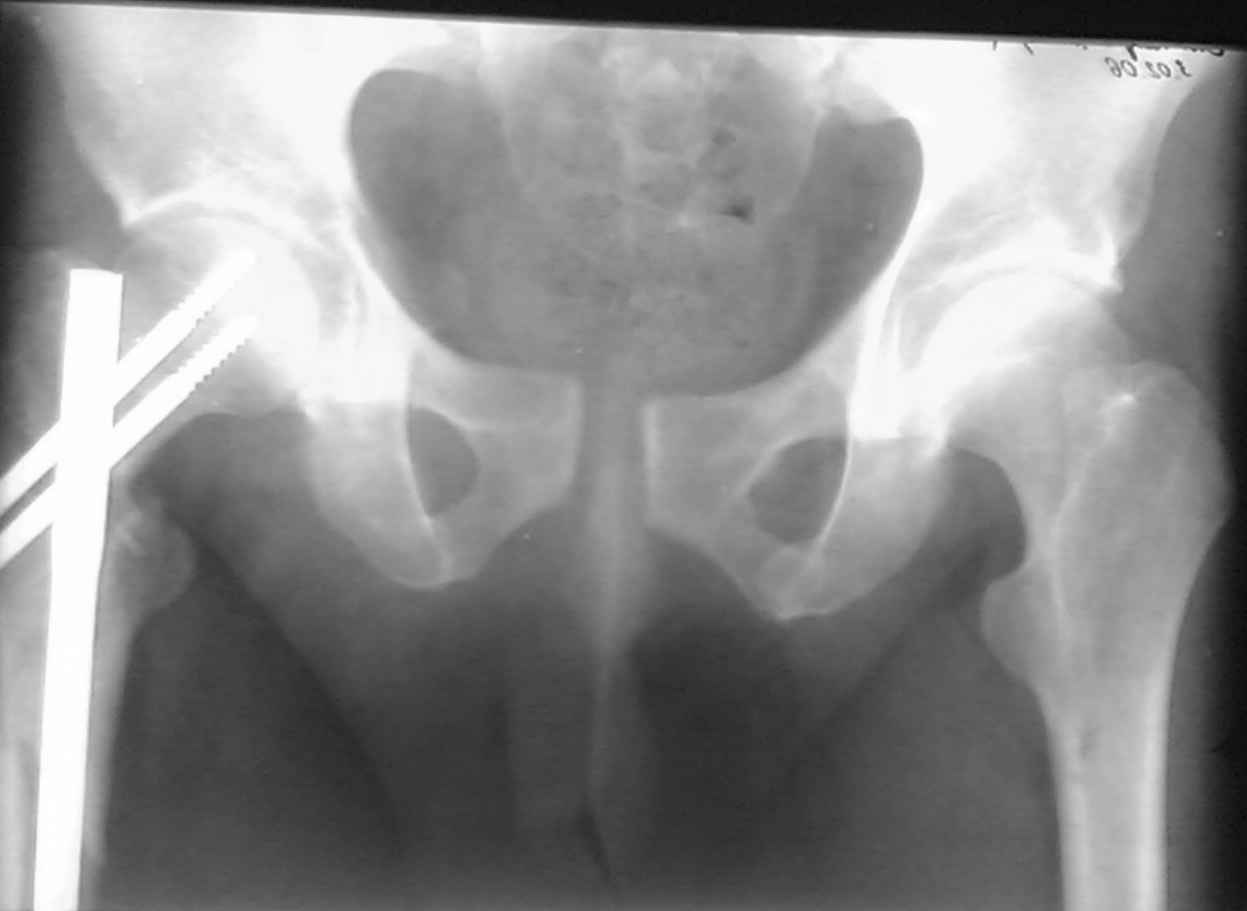

ПЕРЕСМАТРИВАЛ РАЗНЫЕ СНИМКИ И НАШЕЛ НА ЭТУ ТЕМУ ФОРУМА СНИМОК. БОЛЬНОЙ БЫЛ ПРООПЕРИРОВАН НА ПРАВОЕ БЕДРО ПОСЛЕ ЧЕГО СДЕЛАН ТАЗ В ЦЕЛОМ. ВОТ ЧТО НАШЛОСЬ.

КАКОЕ ВАШЕ МНЕНИЕ О ТАКТИКЕ.

ДУМАЮ ПРОШЛО ОКОЛО 10 ДНЕЙ.